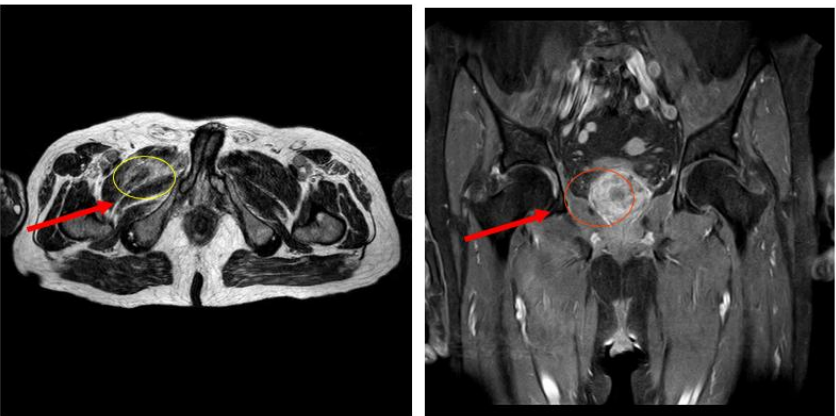

FIGURE 2:     In the T1 and T2 sequences of MR imaging, it was found that the abscess area [(a) yellow circle] decreased significantly and there was no perforation of the prostate capsule [(b) red circle].

Four weeks after the treatment the MRI demonstrated that prostatic capsule was intact and there was a significant reduction in the abscess area. He also denied any pain or symptoms.